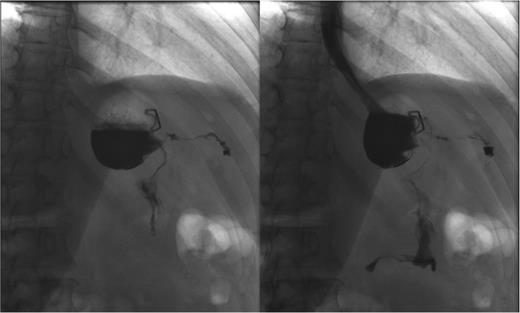

An outpatient OGD, with the intent to close the fistula, was carried out; the tract was defined after injection of contrast and stabilized with two clips (Fig. 1).

Endoscopic attempt to close the fistula. Oesophago-gastro-duodenoscopy sequence that shows the opening point of the fistula (arrow) and its stabilization with clips.